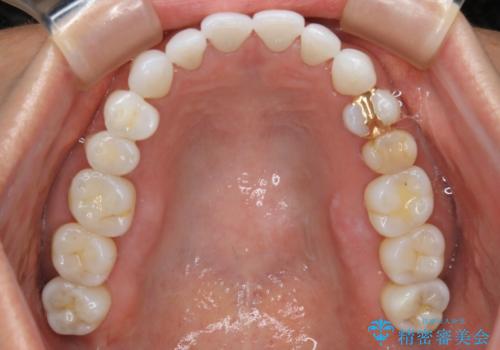

【非抜歯】マウスピースでオープンバイトを治す

- 歯ぎしりや食いしばり、噛み合わせの治療とガタつきを治したいとのことでご来院されました。

検査の結果、前歯と臼歯の高さに差があり、前歯が全く当たらない状態になっているため歯ぎしりによって奥歯が削れてしまっているという状態でした。

マウスピースの矯正装置を用い、ガタつきを治しつつ奥歯を沈めていくことで噛み合わせ全体の改善を図りました。